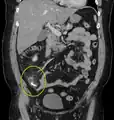

| A fecalith marked by the arrow which has resulted in acute appendicitis. | |

A fecalith is a stone made of feces. It is a hardening of feces into lumps of varying size and may occur anywhere in the intestinal tract but is typically found in the colon. It is also called appendicolith when it occurs in the appendix and is sometimes concomitant with appendicitis.[1] They can also obstruct diverticula. It can possibly form secondary to fecal impaction. A fecaloma is a more severe form of fecal impaction, and a hardened fecaloma may be considered to be a giant fecalith. The term is from Greek líthos=stone.[2]

A small fecalith is one cause of both appendicitis and acute diverticulitis.

Appendicolith as seen on CT